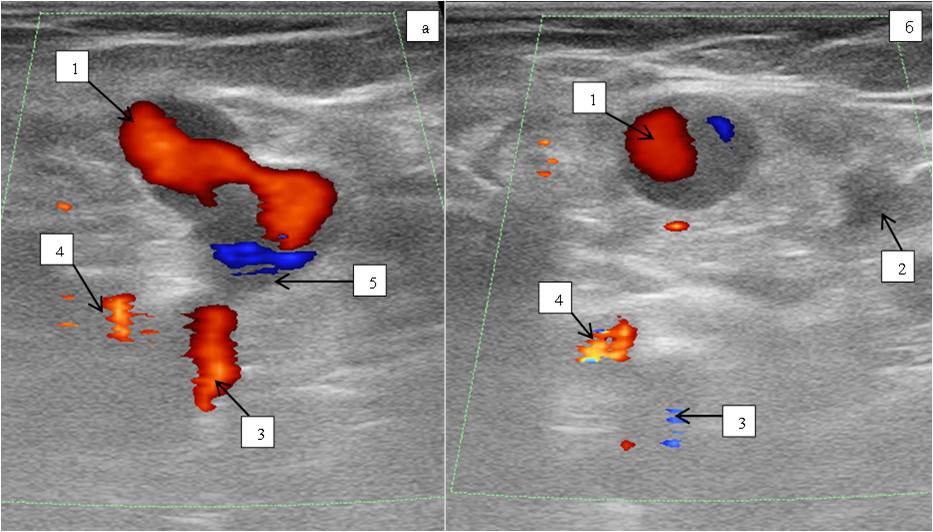

DS of the lower limb veins: deep veins patent, full compression, moderate insufficiency of the common femoral vein valves, other segments of deep veins competent. The SFJ receives the competent GSV and the varicose incompetent anterolateral tributary. SSV patent, competent (Figure 3).

Fig. 3. Female patient Z., 35 years old. US scan of vessels of the saphenofemoral junction at the time of Valsalva test.

Notes: 1 — varicose anterolateral tributary, 2 — great saphenous vein, 3 — common femoral vein, 4 — common femoral artery, 5 — saphenofemoral junction.